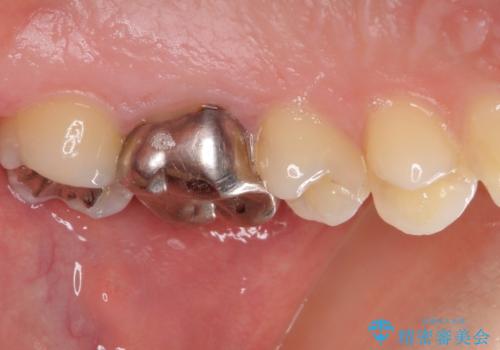

- 奥歯の銀歯の下にあるむし歯治療を希望して来院された患者様です。

口を開けたときに見えてしまう部分はセラミックインレーやジルコニアクラウンに、目立たない部分はゴールドインレーにてむし歯治療を行うこととしました。

機能面を優先すると、PGAインレー(ゴールドインレー)による修復治療やPGAクラウンによる補綴治療が望ましいのですが、笑ったときに見えている銀歯がどうしても気なってしまうとのことで、目立ってしまう奥歯はセラミックインレーやセラミッククラウンを装着することとしました。